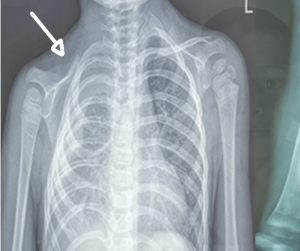

Tutto era cominciato otto mesi prima di quell’Halloween, quando il bambino aveva cominciato ad avvertire dolori diffusi alla schiena. Una notte, poi, si era svegliato di notte molto agitato, senza fiato, ed erano corsi al pronto soccorso. Poggiato il fonendoscopio sulla schiena del bambino, la pediatra aveva notato che nell’emitorace destro i rumori respiratori erano molto ridimensionati rispetto alla norma e gli aveva prescritto una radiografia. L’esame aveva rilevato del liquido all’interno della pleura, il tessuto membranoso che riveste i polmoni. Con grande sorpresa del medico, nelle lastre non si riuscivano a vedere la clavicola destra e alcune vertebre. Alcuni giorni dopo, una biopsia ossea avrebbe chiarito la situazione: alcuni vasi linfatici, attraversando l’osso, avevano creato delle zone di riassorbimento e riduzione del midollo.

La malattia dell’osso fantasma

Questi cambiamenti patologici a carico del tessuto osseo corrispondevano a quelli che si osservano nella malattia rara di Gorham-Stout, comunemente nota come malattia dell’osso fantasma. Si tratta di una patologia molto rara, caratterizzata dallo sviluppo anomalo dei vasi sanguigni e linfatici che causa progressiva distruzione dell’osso. Nel caso di Matteo, la miscela di liquido linfatico e minerali ossei aveva causato un versamento pleurico, il chilotorace, motivo dei suoi problemi respiratori.